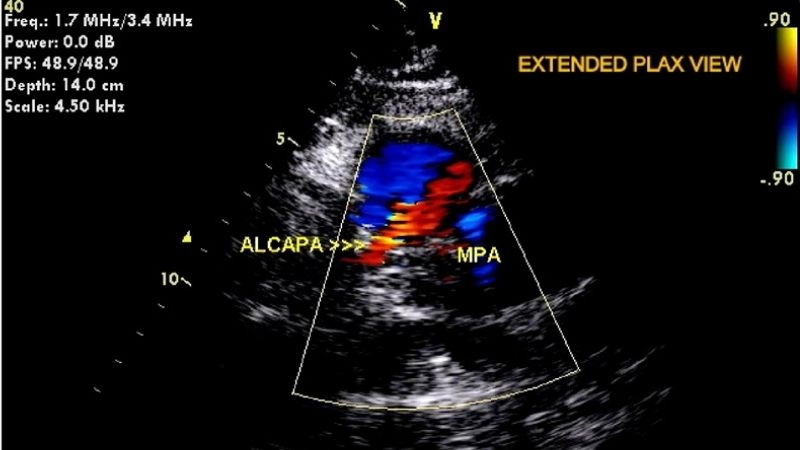

Images visual examples of Anomalous Left Coronary Artery From The Pulmonary Artery (ALCAPA)

Images often illustrate how the left coronary artery abnormally arises from the pulmonary artery instead of the aorta, showing blood flow disruptions and oxygen supply issues in the heart muscle.